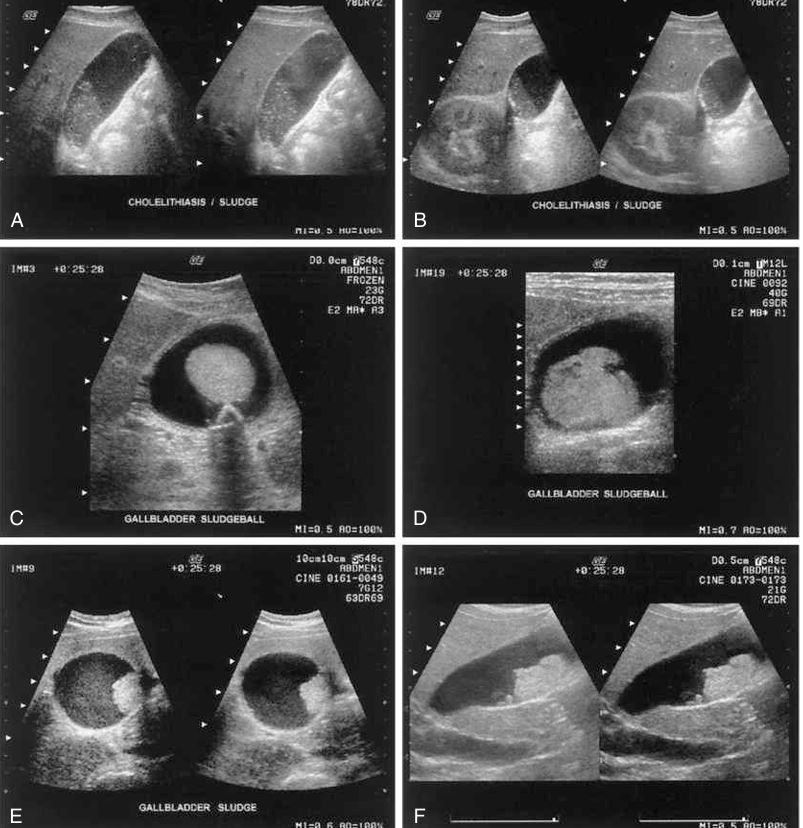

Sludge

different patterns of cholelithiasis

sludge

Cholelithiasis showing multiple small floating and

nonfloating gallstones

patterns of sludge